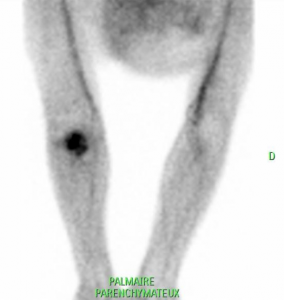

Parenchymateux: Foyer hyperhémique du coude gauche.

Clichés tardif: hyperfixation intense en regard d’un tissu partiellement calcifié de la réinsertion du tendon bicipital qui témoigne du caractère évolutif de l’ostéome. Contre indication chirurgicale.